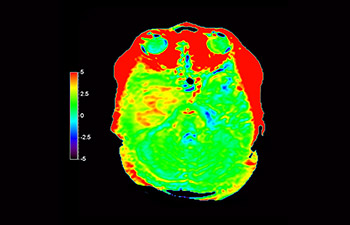

Brain lesion

with 3D APT

3D APT (Amide Proton Transfer) is a unique, contrast-free, brain MR imaging method addressing the need for more confident diagnosis in neuro oncology. 3D APT uses the presence of endogenous cellular proteins, to produce an MR signal that directly correlates with cell proliferation, a marker of tumoral activity. 3D APT can support trained medical professionals in differentiating low grade from high grade gliomas and, in differentiating tumor progression from treatment effect1.